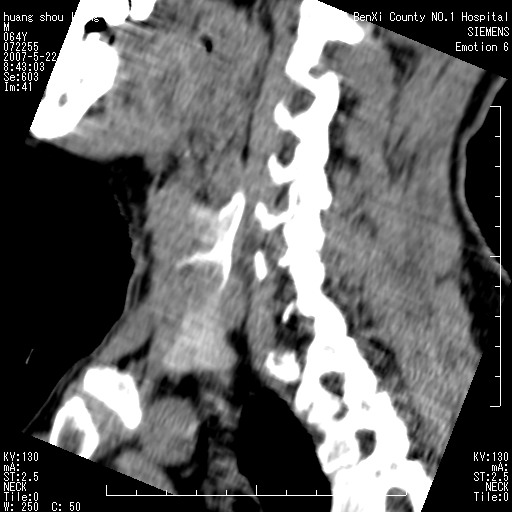

男性,64岁。颈部包块8年。最近增大。

对不起大家,可能是片子发太多有点乱,正常腮腺在下颌角的外侧,颌下腺在下颌体的中部内侧,本例在下颌角内侧偏下,和腺体一点关系都没有,从vrt和mpr上可以很明显看出来,再者肿块是好多粘连在一块的,大家在仔细看看,左侧可能也是吧,我还是考虑为肿大的淋巴结融合在一块,但性质??????

多考虑颌下腺混合瘤恶变,建议进一步检查,另外楼主重建图像很漂亮。

大家好,病理结果出来了,如大家所说,颌下腺混合瘤。

画个图共同讨论一下解剖关系。